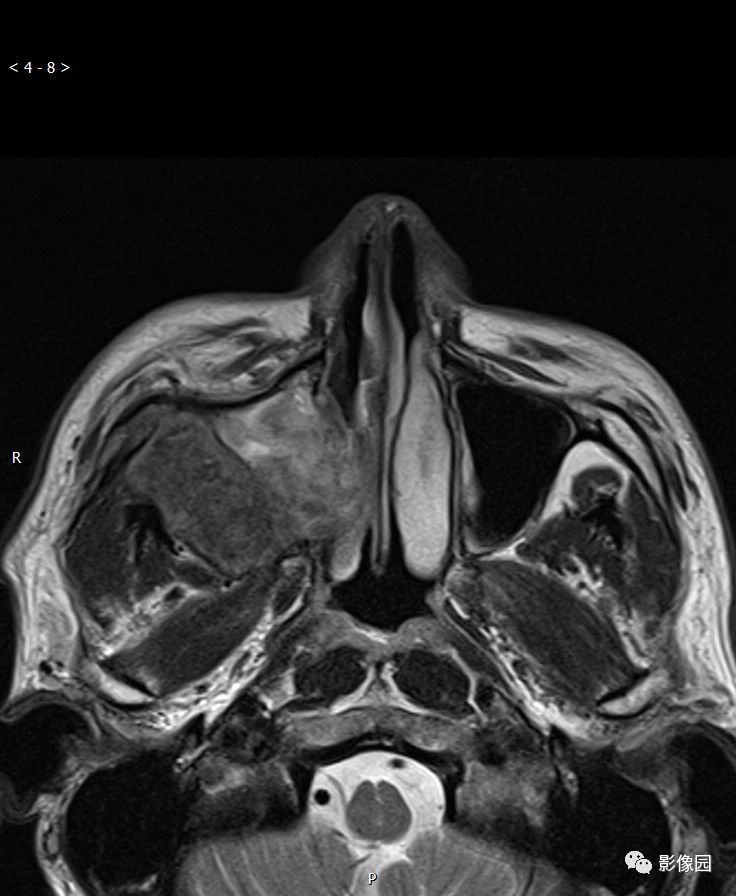

典型右侧上颌窦癌1例